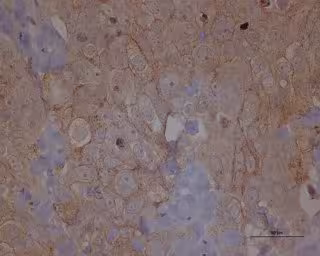

Metástasis cáncer de ovario

IDIBELL-ICO - Archivo